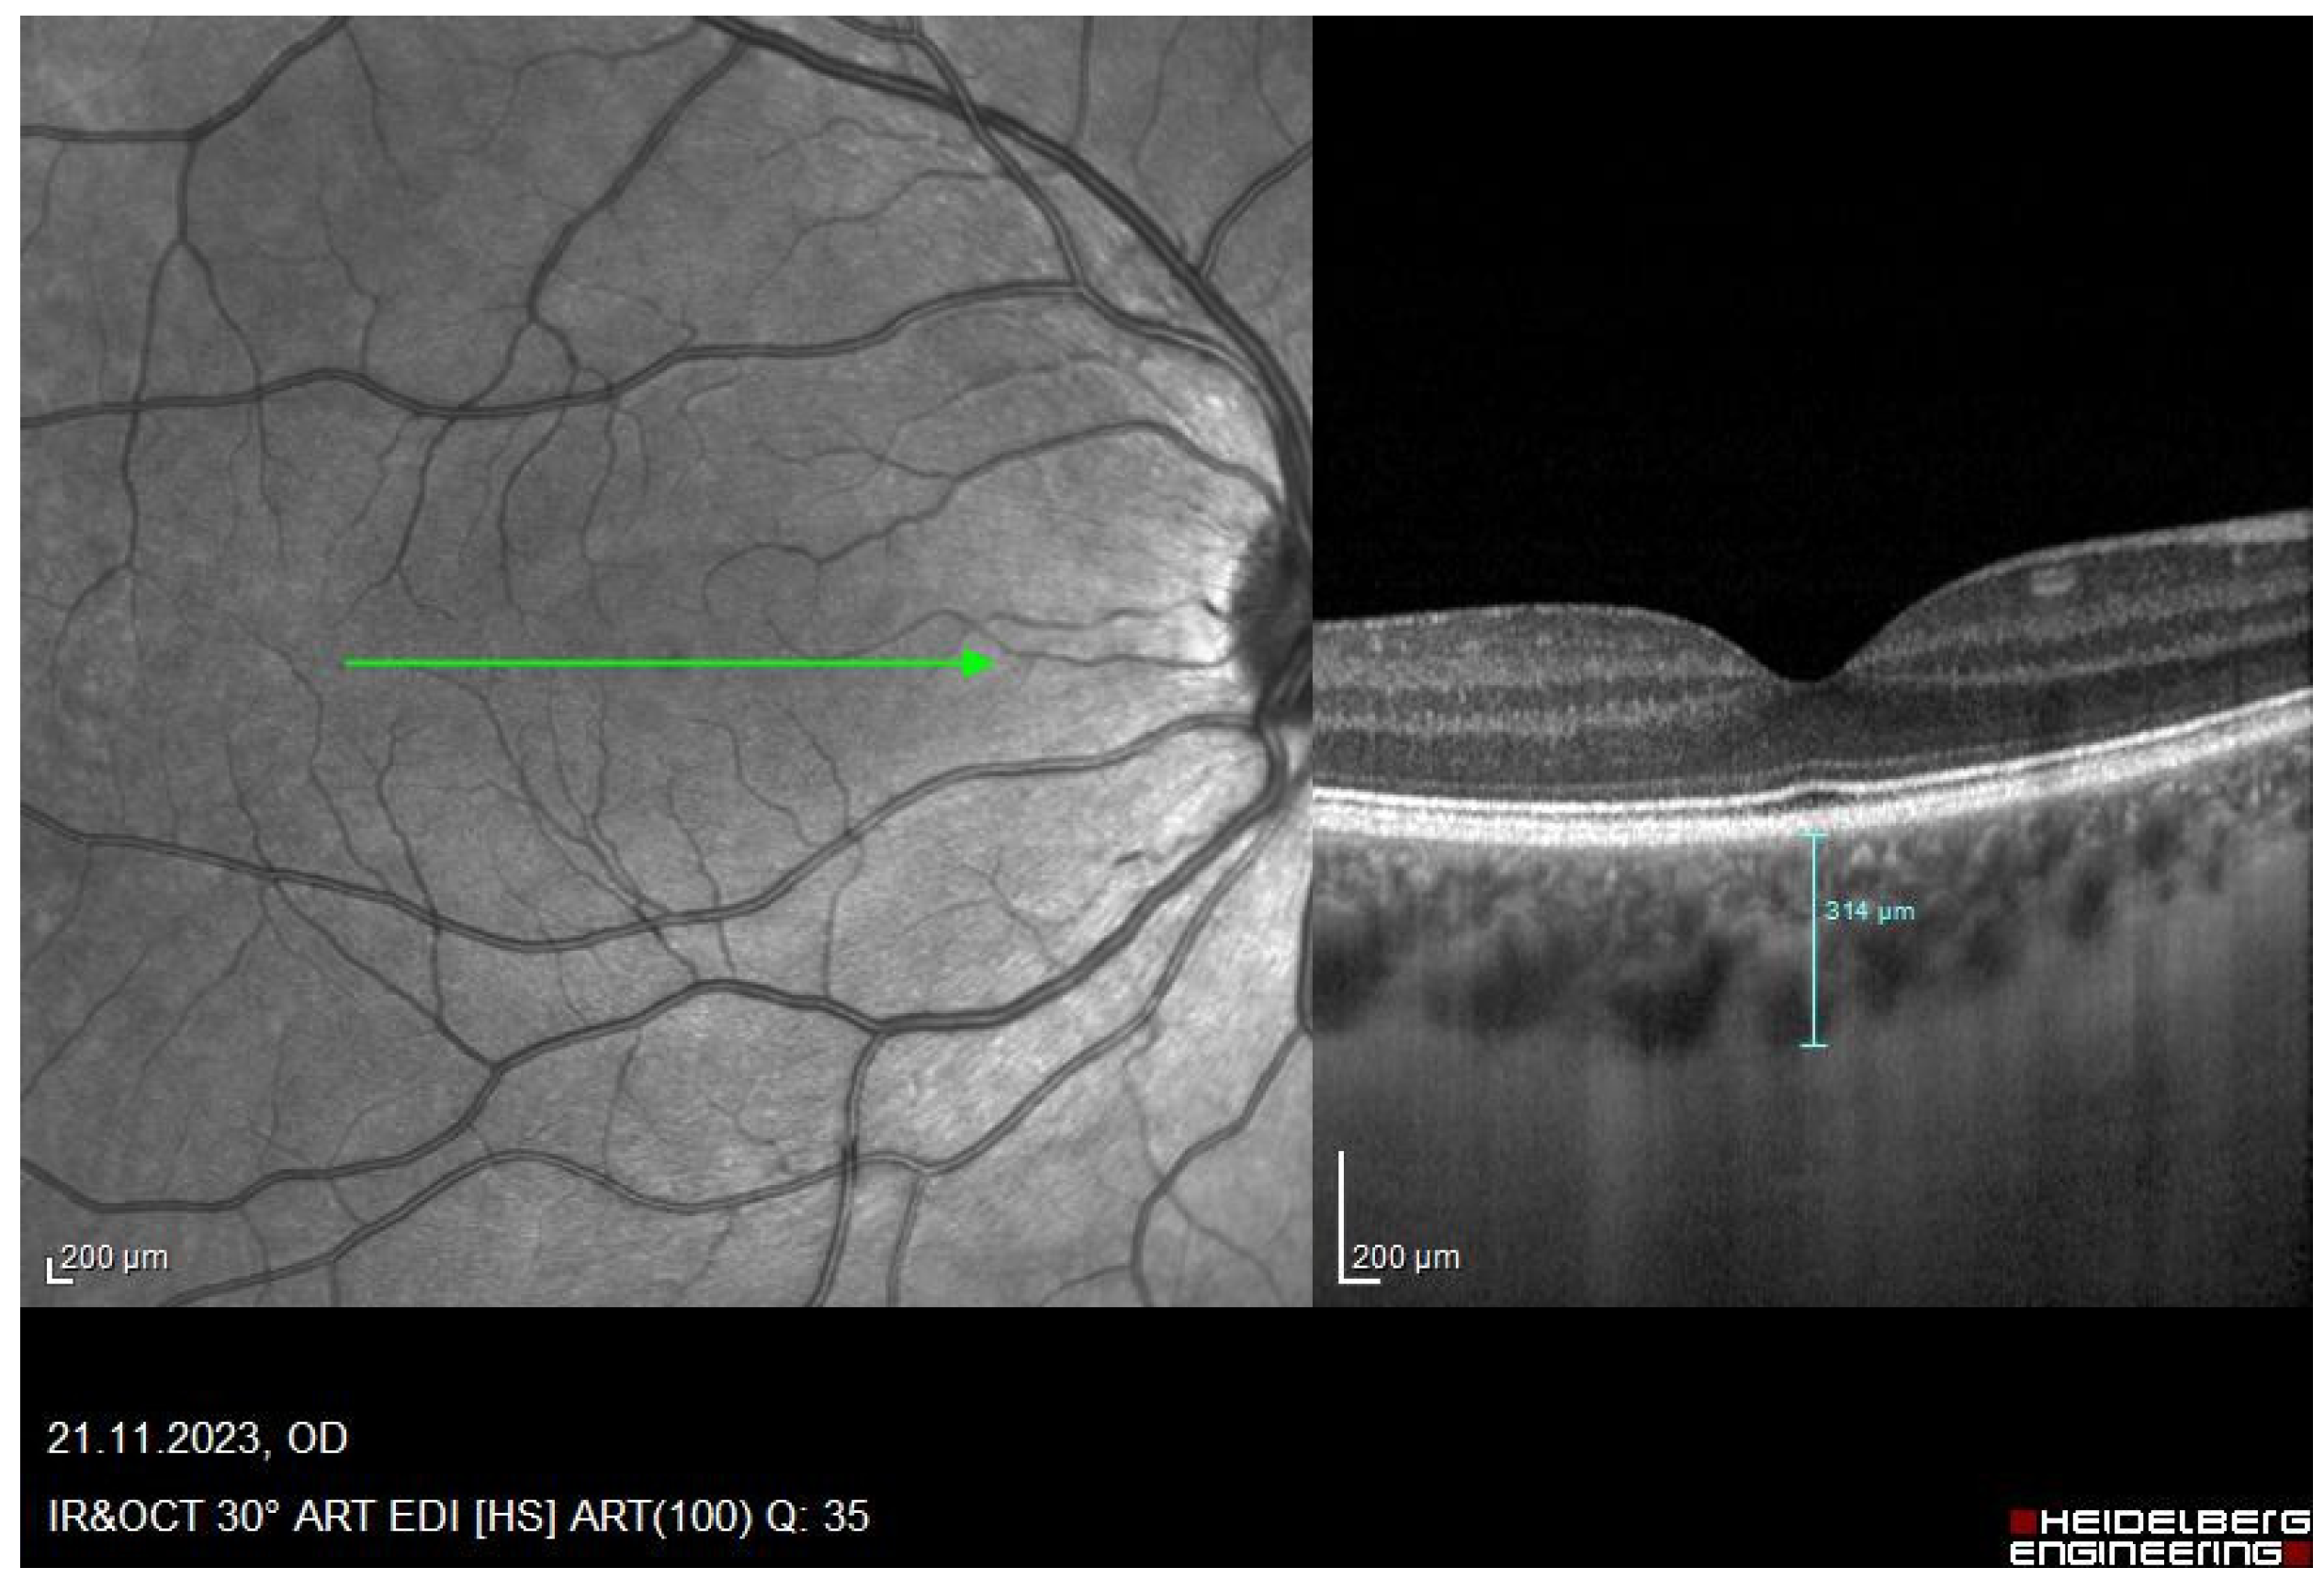

2.2. Measurement Procedure

| SFCHR | Sub-foveal Choroidal Thickness |

| OCT | Optical Coherence Tomography |